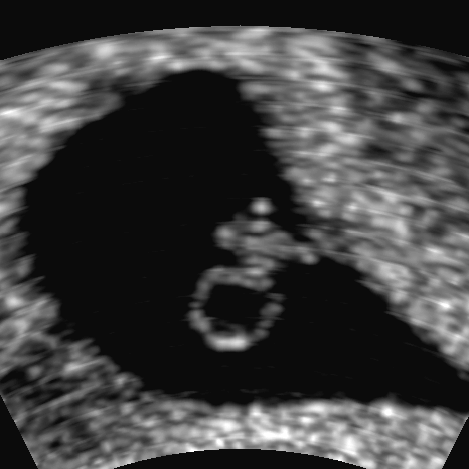

Vierkammerblick

Button

Bildtitel

13. SSW: Fünfkammerblick

Pulmonalisblick